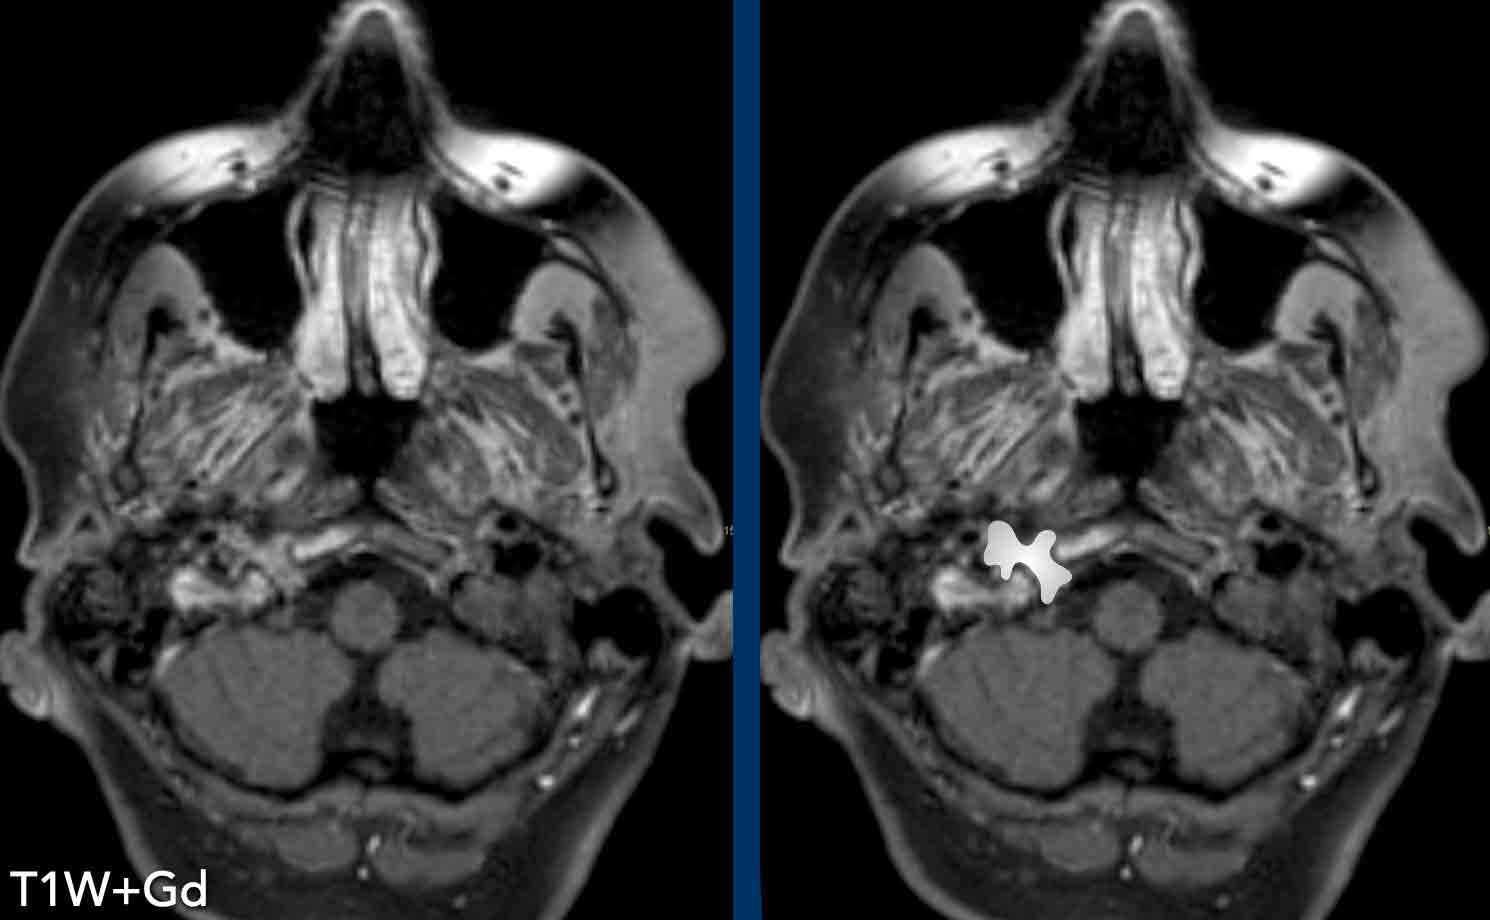

Ca lâm sàng

Những hình ảnh này của một bệnh nhân ung thư tuyến tiền liệt di căn, hiện xuất hiện liệt dây thần kinh hạ thiệt bên phải và hội chứng Horner bên trái.

Hình ảnh

Ống thần kinh hạ thiệt bên trái bình thường.

Bên phải có một khối ngấm thuốc cản quang.

Continue…

Hình ảnh bên phải minh họa khối tăng ngấm thuốc trong ống thần kinh hạ thiệt.

Ống thần kinh hạ thiệt nằm giữa lồi cầu chẩm và củ tĩnh mạch cảnh, chạy chếch ra trước từ sau-trong đến trước-ngoài, cho phép thần kinh hạ thiệt thoát ra khỏi hố sọ sau.

Ở bệnh nhân này với ung thư tuyến tiền liệt di căn, chúng tôi cho rằng đây là một tổn thương di căn.

Tuy nhiên, phát hiện này không giải thích được hội chứng Horner ở bên trái.

Sau đó, chụp CT cổ và ngực được thực hiện, cho thấy một khối trước cột sống ở mức C7-Th1.

Đây chính xác là vị trí của hạch cổ dưới.

A mass in this location explains the Horner on the left.